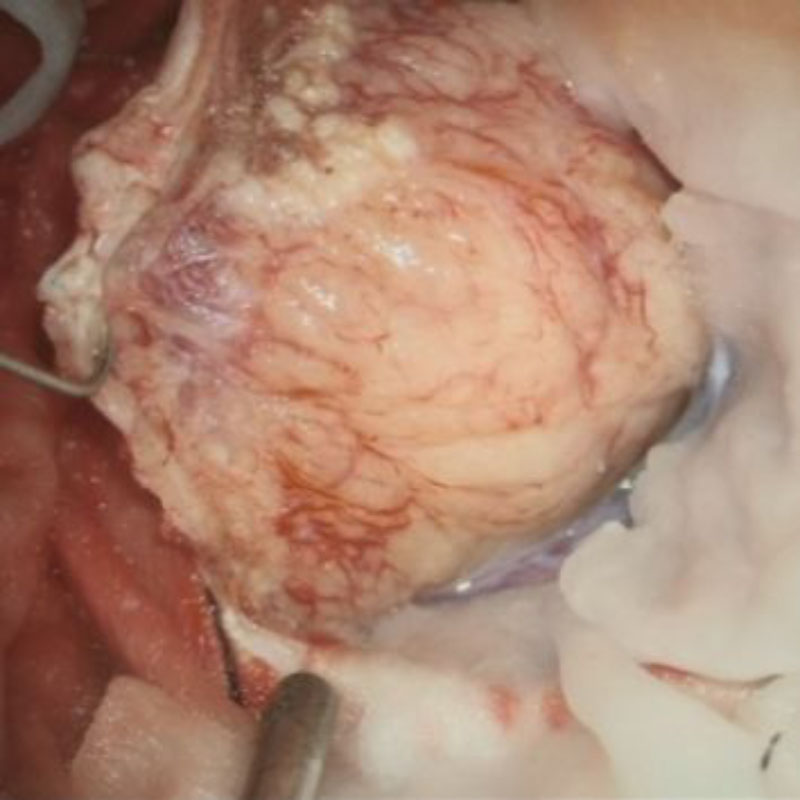

No.’25_88 摘出 後